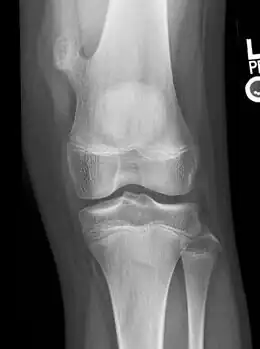

Osteochondroma arising from the large long bone of lower leg, near the knee